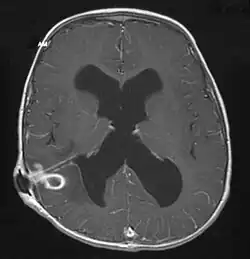

L'abcès peut être visualisé par scanner crânien ou par IRM sous forme d'une cavité entourée d'une coque hyperdense. Les caractéristiques de l'image IRR permettent de distinguer un abcès d'un kyste[9].